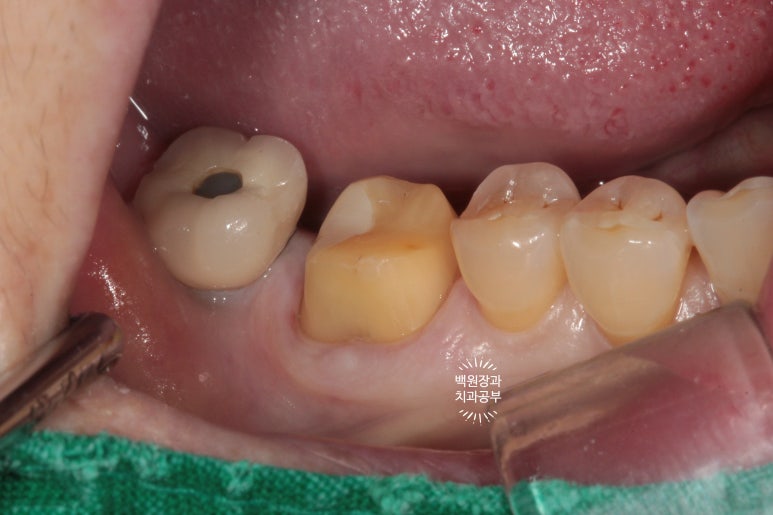

사진상에서 금니가 보이시나요?

떨어져서 가지고 오신 것을 제가 끼워놓은 상태입니다.

왜냐! 2차충치가 있음을 더욱 명확히 보여드리기 위해서입니다.

빨간색으로 보이는 것은 음식물입니다.

오래 전에 붙여놓은 골드 인레이 주변으로 2차 치아우식증 (2차 충치)가 발생하여 그 틈으로 접착제가 녹아 골드인레이가 떨어진 것이었어요.

저 골드인레이를 제거하면 하방에 분명한 2차 충치가 있습니다.!!!